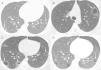

A 17-year-old male was admitted to the Emergency Department with cough and episodes of hemoptysis. The patient had a history of a giant cell tumor (GCT) in the left tibia, resected 6 months previously. Chest computed tomography (CT) revealed pulmonary nodules, some of which were cavitated (Fig. 1A). Laboratory test findings were unremarkable. The patient's sputum was negative for acid-fast bacilli. He was referred for fiberoptic bronchoscopy with bronchoalveolar lavage. The bronchoalveolar lavage fluid contained a small amount of blood, and was negative for neoplastic cells. Cultures were negative for fungus and bacteria. Video-assisted thoracoscopy was performed, and the biopsy findings from one of the nodules were compatible with GCT metastasis. The patient started a new chemotherapy cycle. Four months later, he had an episode of chest pain associated with hemoptysis. A new CT examination showed a left pneumothorax, and cavitated thick-walled nodules with ground-glass halos (Fig. 1B and C). The pneumothorax was drained. The patient evolved well, with pulmonary re-expansion. Eight months later, he had a new episode of chest pain and dyspnea. CT showed a spontaneous left pneumothorax, and evolution of the cavitated nodules into thin-walled cysts (Fig. 1D). In this phase, the patient presented metastasis to intraabdominal lymph nodes in addition to the pulmonary metastases. He underwent new chest drainage and pleuroscopy with bilateral pleurodesis through the intrapleural instillation of talc. During pleuroscopy, pleural metastases were detected. The patient underwent a chemotherapy regimen with six cycles of doxorubicin and cisplatin, which resulted in regression of some of the lung lesions. He remains in outpatient follow-up with no new complication 1 year after the last pneumothorax.

(A) Axial chest CT with pulmonary window settings shows bilateral small pulmonary nodules, two of which are cavitated (arrows). (B, C) CT performed 4 months later demonstrates a left spontaneous pneumothorax (asterisk) and growth of the nodules, which now present with relatively thick walls and ground-glass halos (arrows). (D) CT performed 1 year after A shows a new left pneumothorax (asterisk) and evolution of the cavitated nodules into thin-walled cystic lesions (arrows).